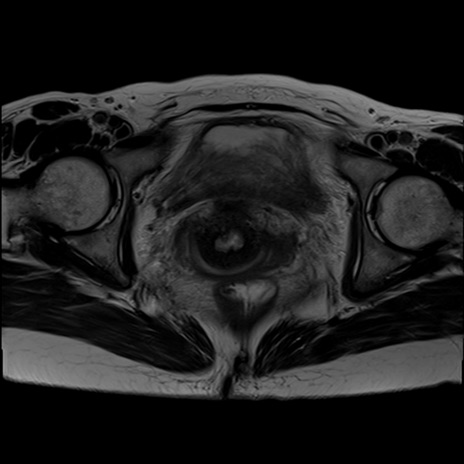

症例39 T2WI(横断像)

MRI(4日後)